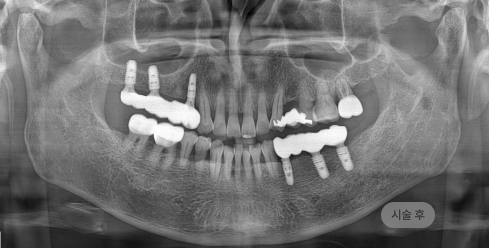

화면을 드래그하여 전/후를 비교해 보세요